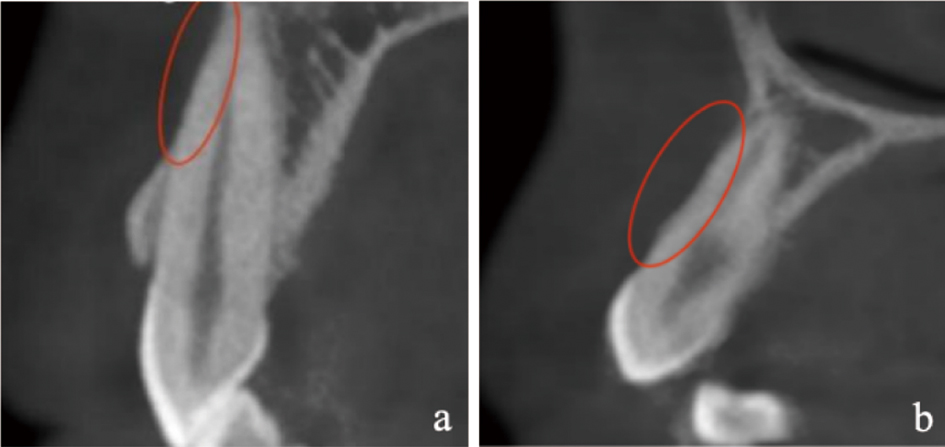

Han SB, Fan XF, Wang S, et al. Dehiscence and fenestration of skeletal Class Ⅲ malocclusions with different vertical growth patterns in the anterior region: A cone-beam computed tomography study[J]. Am J Orthod Dentofacial Orthop, 2024, 165(4): 423-433.

Lei C, Yu Q, Wu D, et al. Comparison of alveolar bone width and sagittal tooth angulation of maxillary central incisors in Class Ⅰ and Class Ⅲ canine relationships: A retrospective study using CBCT[J]. BMC Oral Health, 2022, 22(1): 303.

Rodrigues DM, Petersen RL, Montez C, et al. The relationship between tomographic sagittal root position of maxillary anterior teeth and the bone housing[J]. J Prosthet Dent, 2023, 130(5): 705-714.

Evangelista K, Vasconcelos KD, Bumann A, et al. Dehiscence and fenestration in patients with Class Ⅰ and Class Ⅱ Division 1 malocclusion assessed with cone-beam computed tomography[J]. Am J Orthod Dentofacial Orthop, 2010, 138(2): 133.e1-133.e7;discussion 133-135.